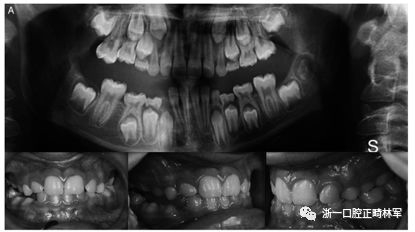

圖2.口內(nèi)照片。全景:外顯子10中的同義變體(位置3:46899419)c.1152 G>A.

兄弟姐妹被診斷為I型PFE并顯示雙邊呈現(xiàn)。該變體(PTH1R基因的外顯子5的下游c.313×32 A.G)發(fā)生在與轉(zhuǎn)錄因子相互作用的調(diào)節(jié)區(qū)中。除了這種突變之外,這些兄弟還受到第二個突變的影響,這些突變對每一個都是獨特的:一個兄弟姐妹(II:1)也存在在外顯子16的基因氨基末端發(fā)生的移碼缺失,c.1593DelC ,第(Pro532Leufs *)(圖1A,B)。在另一個同胞(II:3)中,鑒定出在蛋白質(zhì)氨基酸序列水平不引起變異的外顯子,c.1152GA(rs200475872;圖1A,B)中的同義變體,但涉及改變含氮堿。基于計算機分析,這種改變可能會影響mRNA的折疊并影響其半衰期和蛋白質(zhì)生產(chǎn)。在這個患者樣本中,在一個孤立的病例中發(fā)現(xiàn)了同樣的同義變體c.1152G.A,由于PFE而具有嚴(yán)重的開合(圖2)。

本研究中確定的低咬合的臨床特征與PFE基于基因診斷和萌出障礙診斷標(biāo)準(zhǔn)的應(yīng)用相一致。對特定相關(guān)牙科特征的仔細(xì)臨床檢查包括以下內(nèi)容:至少一顆牙包括低咬合,局限于后部區(qū)域,單側(cè)(38%;圖1A)和雙側(cè)呈現(xiàn)(35%;圖1B和2),至少有一個暫時性后牙(48%暫時;圖1A,B和3A; 55%永久性,圖3B)。此外,觀察到牙面特征如下:由于受影響側(cè)的側(cè)向開放咬傷的嚴(yán)重程度而引起的垂直骨骼不對稱(35%;圖1A,B和圖3A,B);由下頜骨側(cè)向偏離組成的面部不對稱(圖1A,B和圖2;表4)。這種不對稱在單側(cè)開合患者中更為明顯。進一步發(fā)現(xiàn)受影響的患者與先前報道的患者存在上頜骨收縮和III類牙齒/骨骼關(guān)系(28%;圖1A,B和圖2)。至少有一例患者出現(xiàn)了相對于9名患者的低咬合。表4總結(jié)了PTH1R的表型結(jié)果和相關(guān)的突變分析(N = 8)。